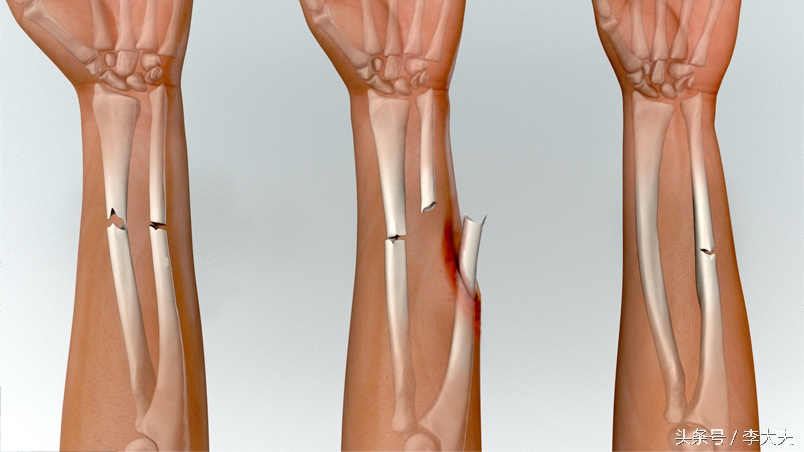

上肢前臂双骨折

上肢双骨折X线片